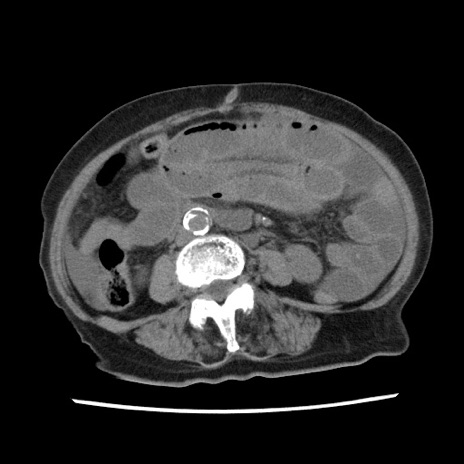

症例1(横断像)

【症例】80歳代女性

【主訴】腹痛

【現病歴】8時間前から腹痛あり来院。

【既往歴】糖尿病、脂質異常症、子宮体癌にて子宮全摘術

【身体所見】意識清明・会話良好だが腹痛で苦悶様、全腹部にわたって反跳痛と圧痛あり

【データ】WBC 13600、CRP 0.14、LDH 224、CK 90